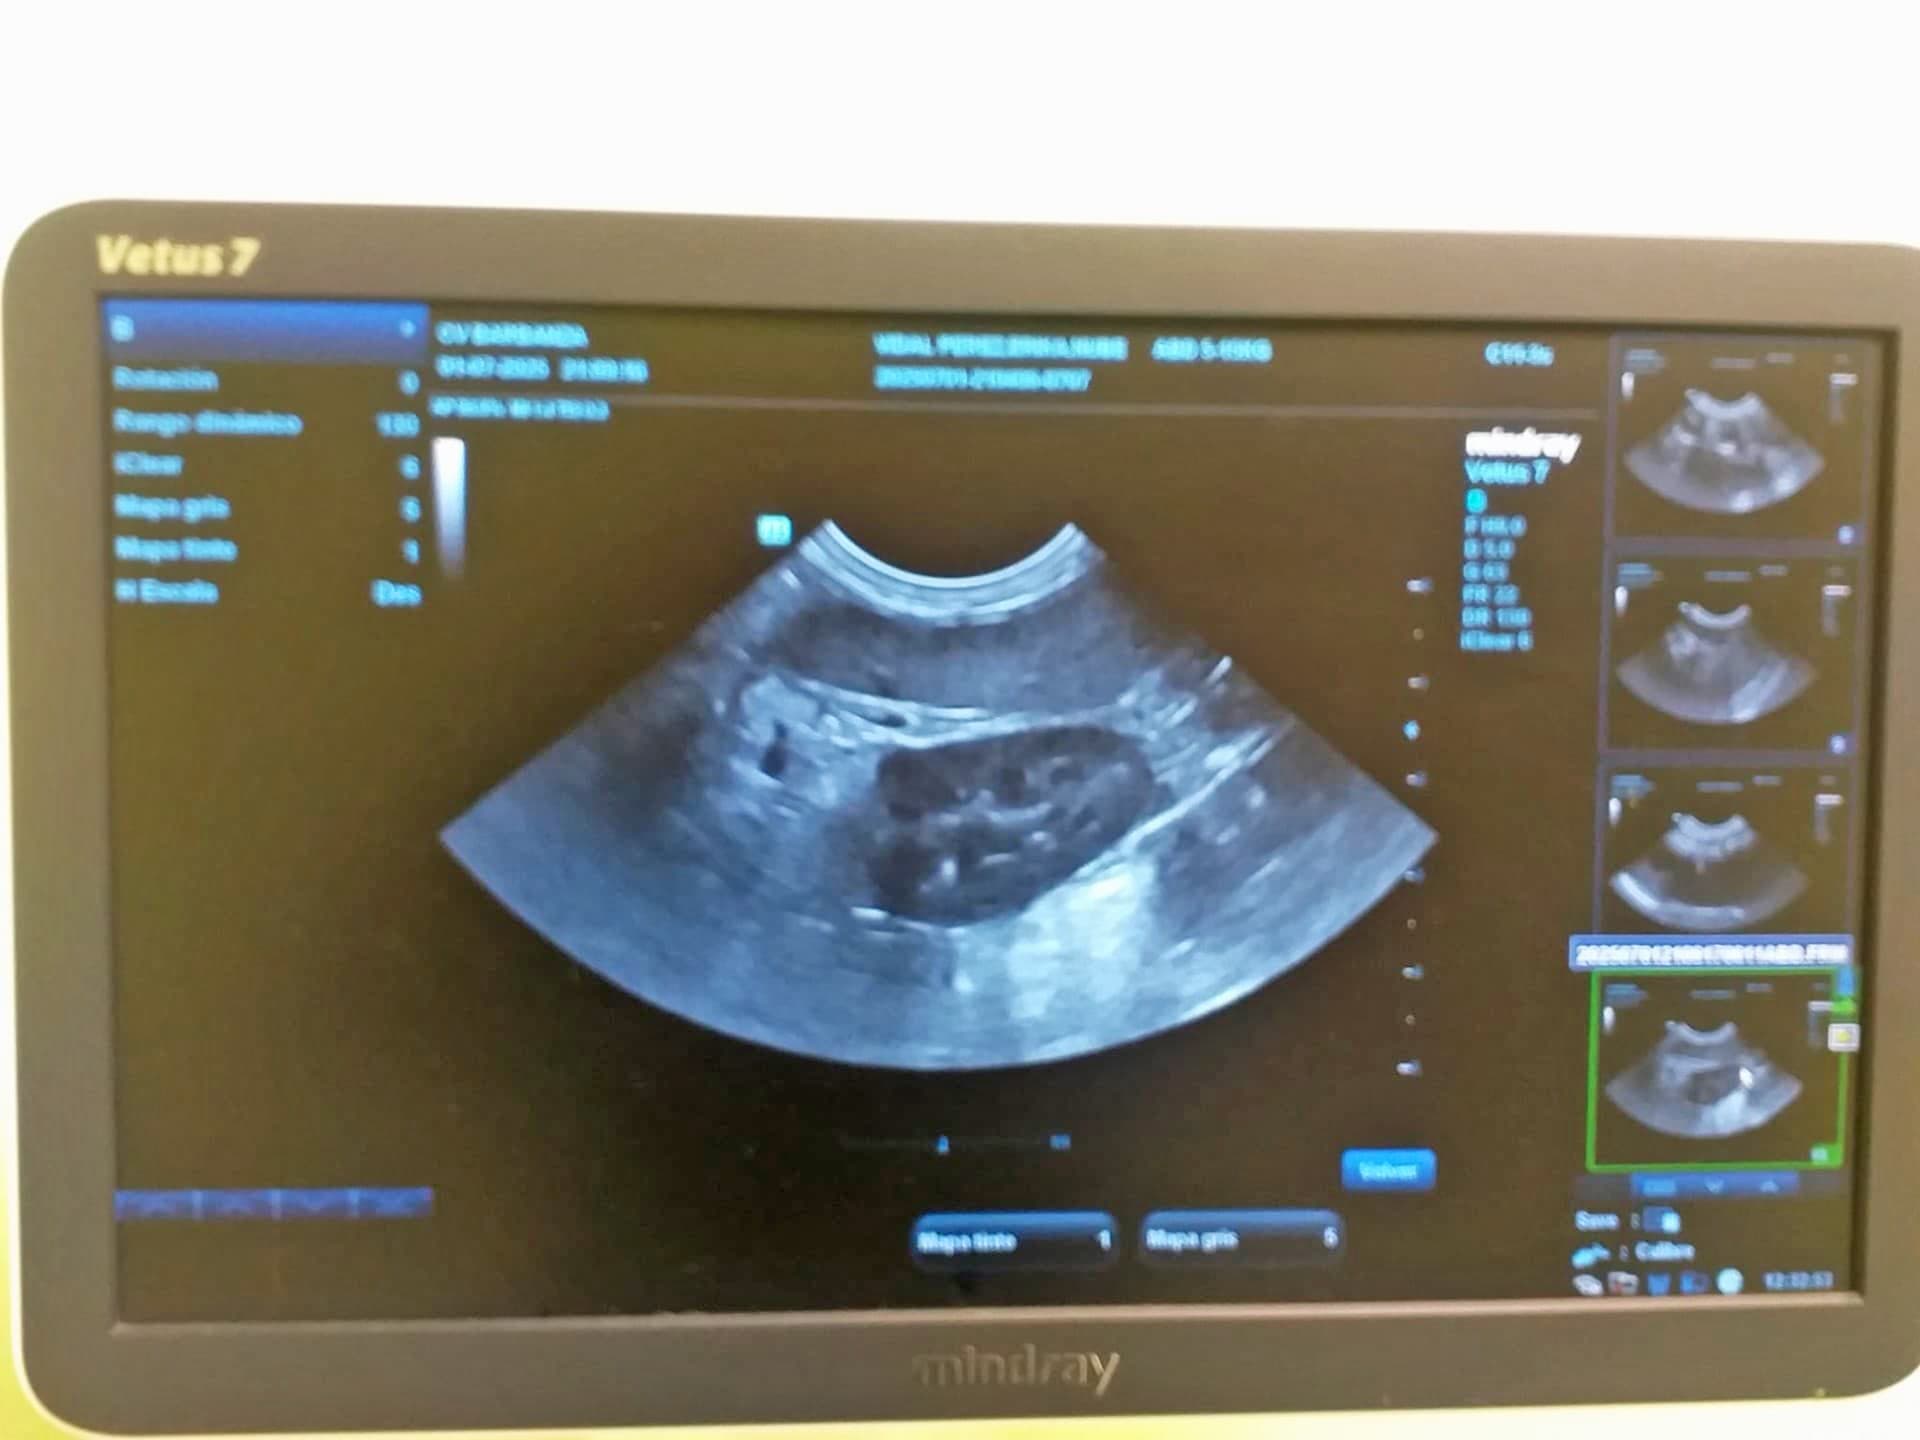

Servicio de ecografía en Boiro para perros, gatos y otros animales

La ecografía es una técnica basada en los ultrasonidos que permite una exploración rápida, no invasiva y que no produce molestias al animal ni resulta nociva. En el Centro Veterinario Barbanza disponemos de la tecnología necesaria para realizar una ecografía a tu gato, a tu perro o a cualquier animal que permita conocer cualquier problema que pueda tener, en el menor tiempo posible.

Gracias a este procedimiento, el veterinario puede diagnosticar anomalías morfológicas y estructurales de los órganos y tejidos del animal, que se pueden corresponder con problemas que van desde los tumores hasta el diagnóstico de cuerpos extraños. La ecografía veterinaria que hacemos en Boiro también se utiliza habitualmente para hacer el seguimiento de una gestación y observar su correcta evolución.

La ecografía en un gato, perro u otro animal es una herramienta esencial en la detección y seguimiento de embarazos. Con esta técnica, podemos monitorizar el desarrollo de los fetos y detectar cualquier complicación.

La ecografía en un perro o gato es fundamental para diagnosticar enfermedades en órganos como el hígado, riñones, vesícula biliar, bazo y tracto gastrointestinal, mejorando mucho las posibilidades de recuperación.

Ecografía para perro en Boiro

Ecografía para gato en Boiro